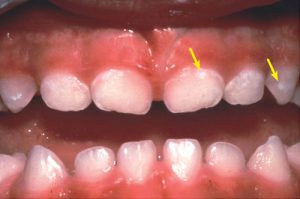

Очаговая деминерализация эмали (белое кариозное пятно, начальная стадия кариеса) — одна из самых ранних клинически диагностируемых стадий кариеса зубов. В клинике проявляется в виде матовых серовато-белых пятен с нечеткими границами, тусклого оттенка, обычно располагающихся в области шейки зуба, жевательной поверхности фиссур. Величина пятна может колебаться от еле различимого до занимающего по площади половину поверхности зуба.

Клинические наблюдения показывают, что чем больше размер пятна, выше его проницаемость, тем более активно течет очаговая деминерализация эмали. При далеко зашедшем процессе наблюдается нарушение рисунка перикиматий на поверхности эмали, свидетельствующие о поверхностной очаговой деминерализации.